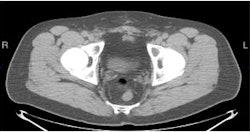

| PET/CT with anti-F-18 FACBC (below) shows left obturator lymph node better than CT (top) and PET (above) images alone. |

Another research study being presented at the SNM conference this week involves a new molecular imaging agent that could improve the diagnosis of recurrent prostate cancer and determine the best possible course of treatment for patients.

The agent, developed by Mark Goodman, MD, at Emory University in Atlanta, consists of a fluorine-based radioisotope paired with a synthetic amino-acid analog similar to the naturally occurring amino acid L-leucine (anti-F-18 FACBC).

Not only was the agent shown to be highly accurate in differentiating recurrent tumors in the prostate from metastatic cancer, but researchers believe the agent could help change patient treatment and improve the prognosis for prostate cancer patients.